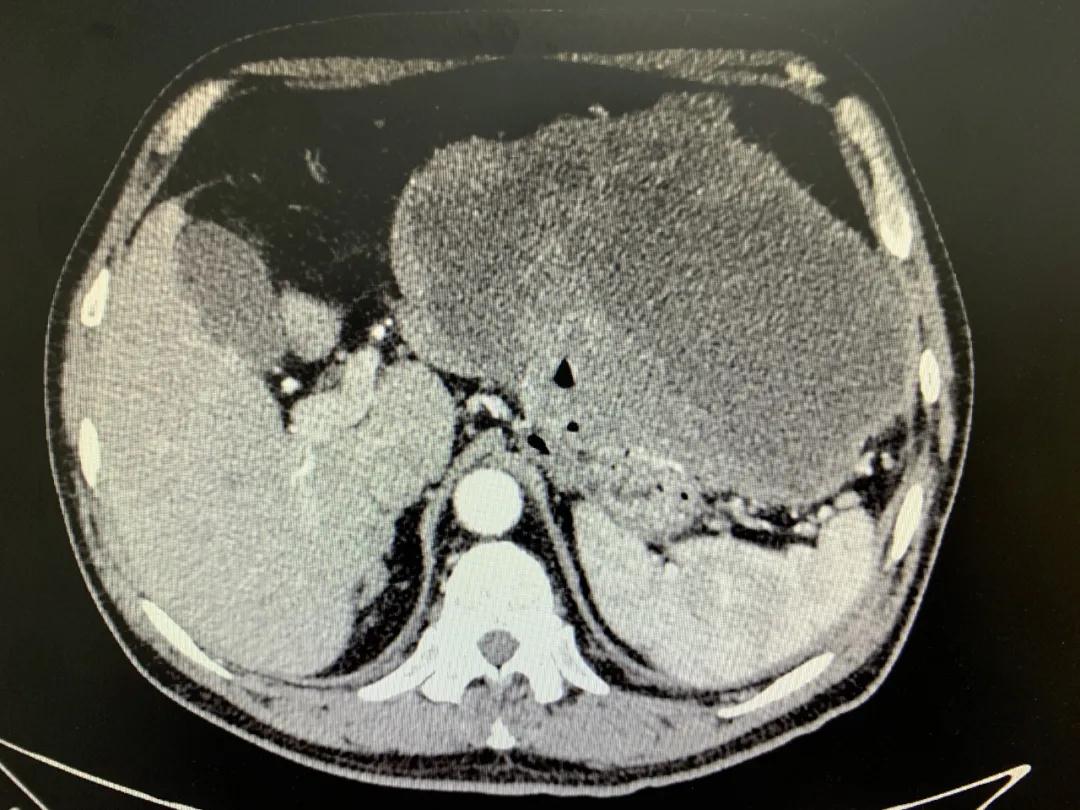

患者入院時血紅蛋白數(shù)值仍持續(xù)下降,出現(xiàn)失血性休克表現(xiàn),危及生命。消化外科二病區(qū)蔡磊主任接診后,組織科室迅速對患者進(jìn)行了全面的檢查。CT提示腫瘤大小約19.3*10.3cm,腫瘤內(nèi)提示大量積血。結(jié)合相關(guān)檢查,考慮為罕見的巨大胃間質(zhì)瘤合并出血。